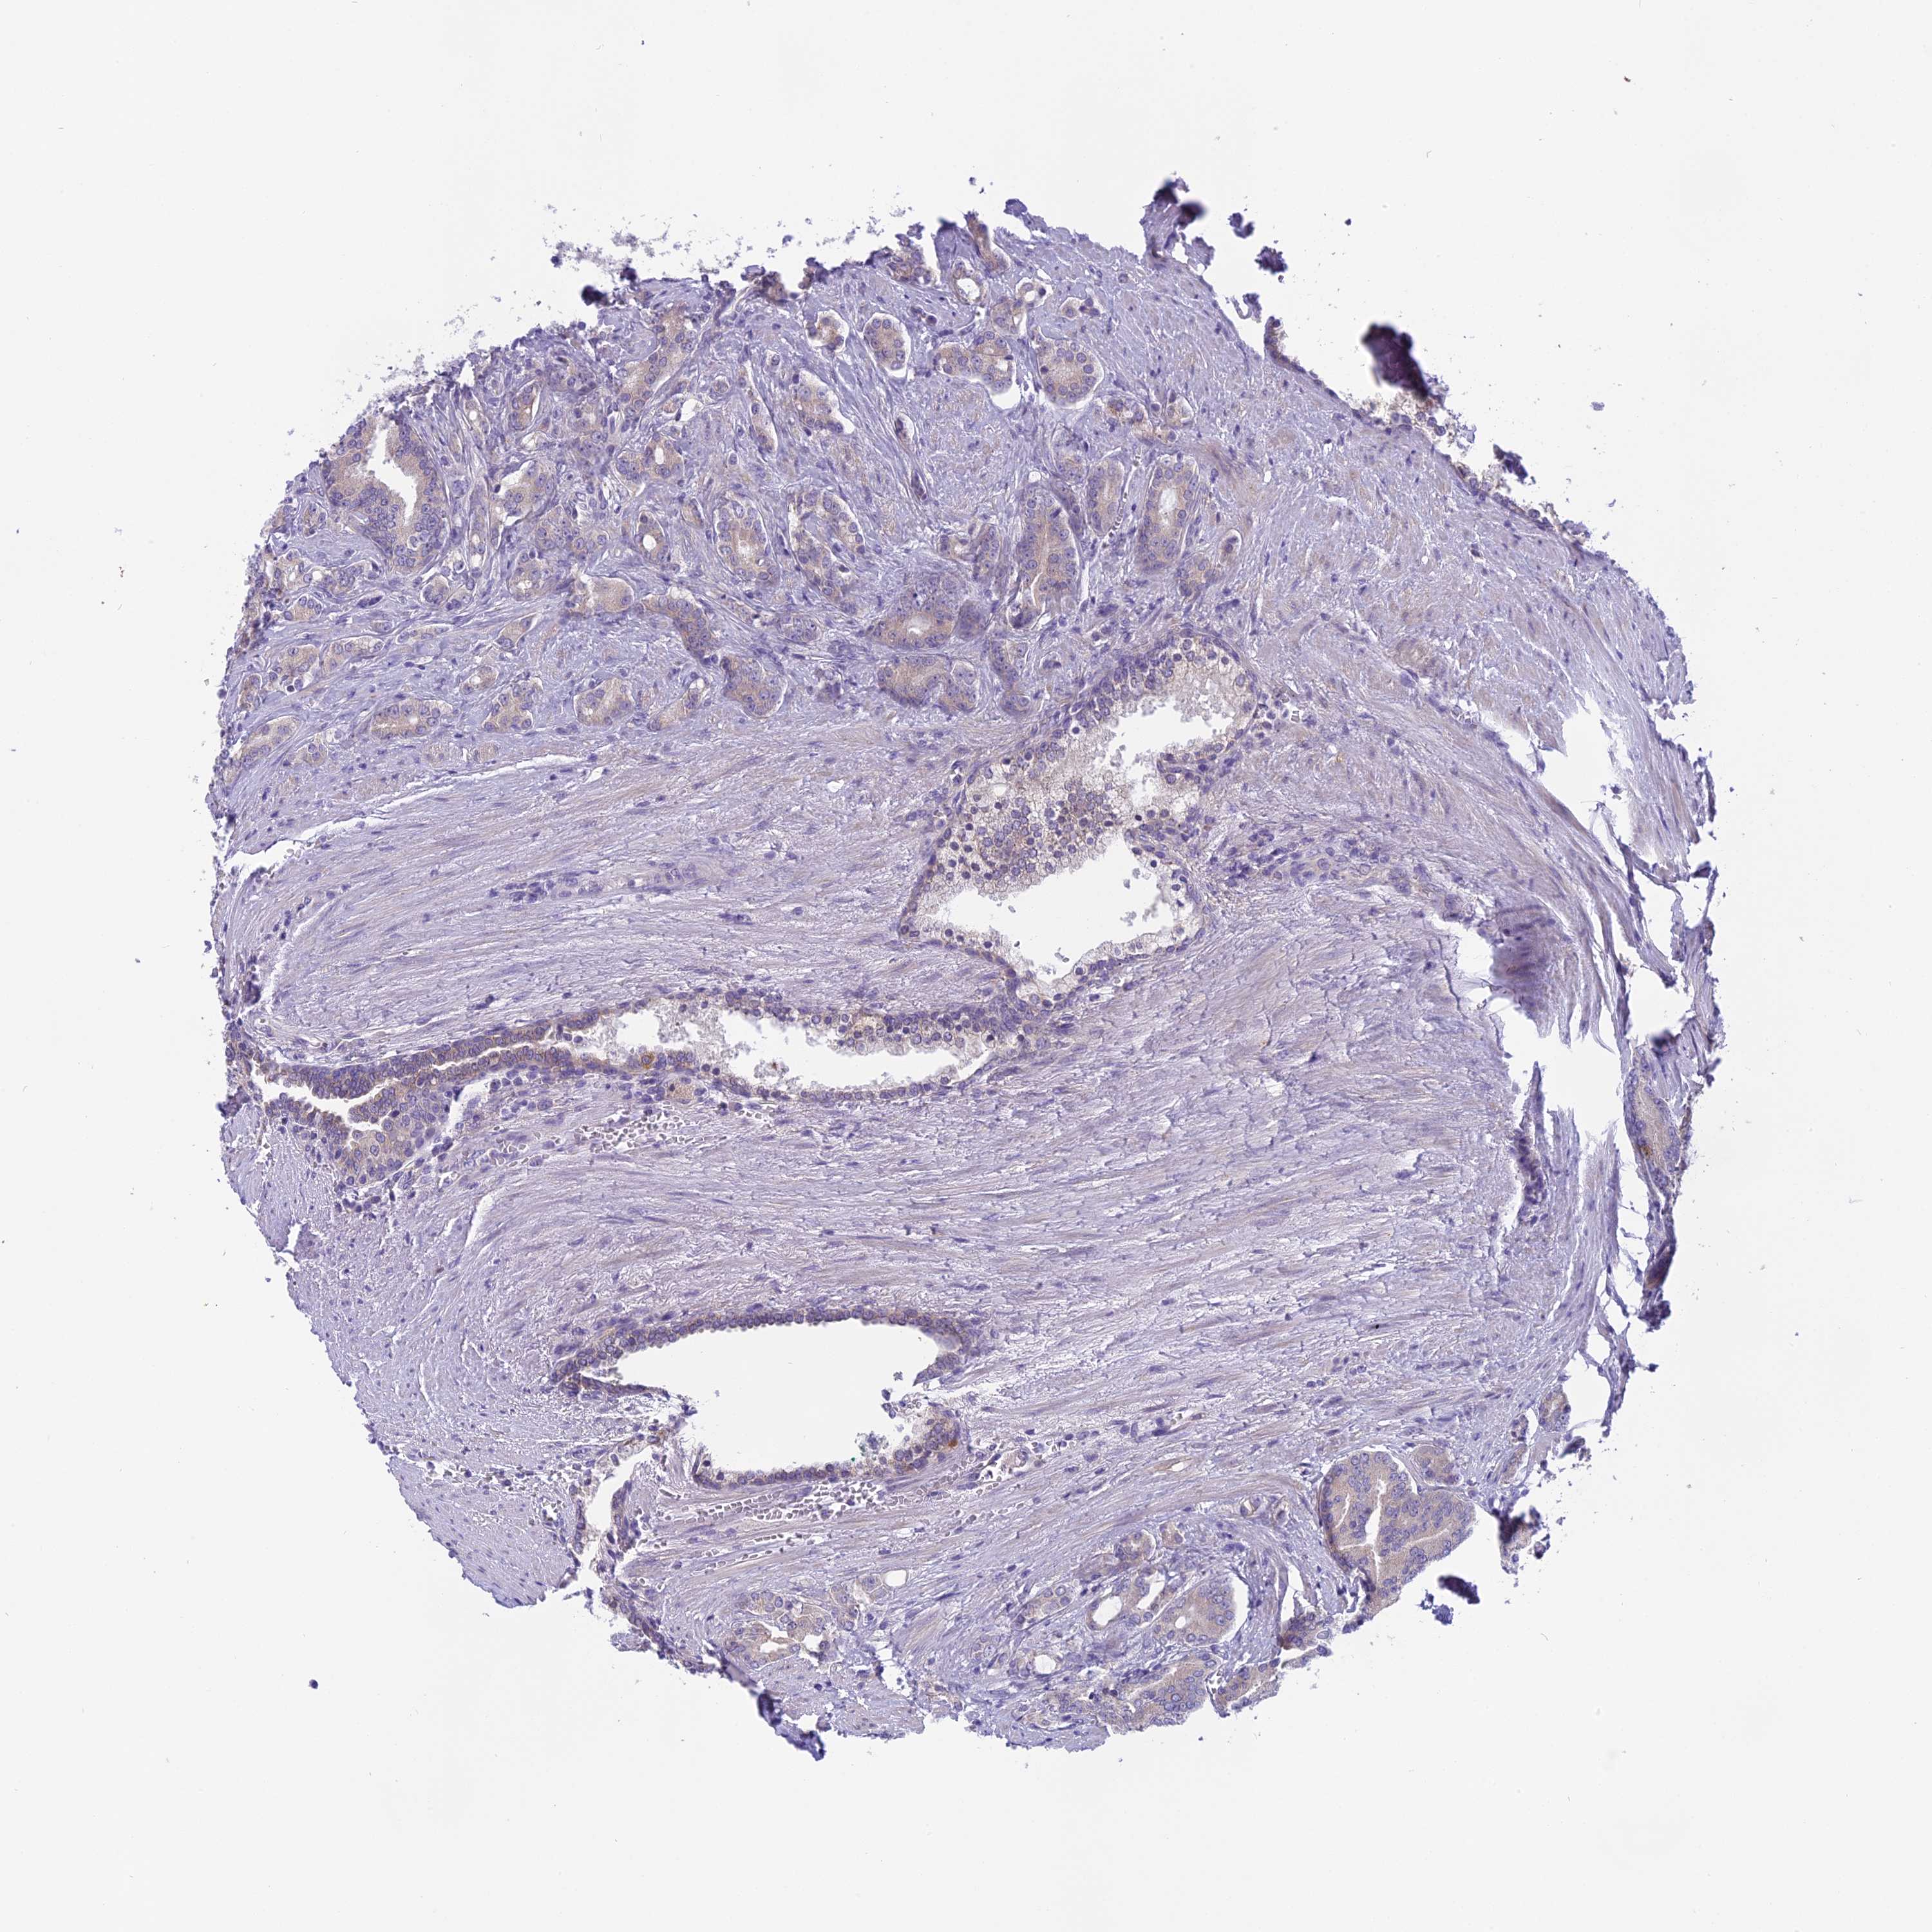

PROSTATE CANCER - Protein expressioni

A mouse-over function shows sample information and annotation data. Click on an image to view it in a full screen mode. Samples can be filtered based on level of antibody staining by selecting one or several of the following categories: high, medium, low and not detected. The assay and annotation is described here.

Note that samples used for immunohistochemistry by the Human Protein Atlas do not correspond to samples in the TCGA dataset.

Antibody stainingi

Antibody staining in the annotated cell types in the current human tissue is reported as not detected, low, medium, or high, based on conventional immunohistochemistry profiling in selected tissues. This score is based on the combination of the staining intensity and fraction of stained cells.

Each image is clickable and will lead to virtual microscopy that enables deeper exploration of all samples and also displays staining intensity scores, fraction scores and subcellular localization as well as patient and tissue information for each sample.

Antibody HPA043885

Antibody HPA053487

Staining

High

Medium

Low

Not detected

Intensity

Strong

Moderate

Weak

Negative

Quantity

>75%

75%-25%

<25%

None

Location

Nuclear

Cytoplasmic/membranous

Cytoplasmic/membranous,nuclear

Adenocarcinoma, NOS

Adenocarcinoma, High grade

Adenocarcinoma, Low grade